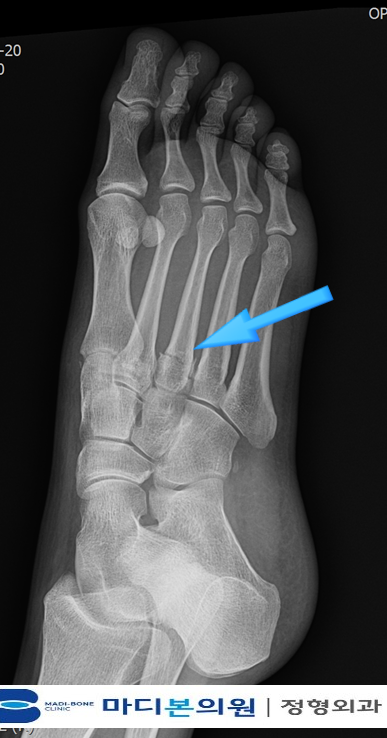

What Is a Hidden or “Occult” Fracture?

A hidden fracture is a break in the bone that is not clearly visible on initial X-ray imaging,

yet causes persistent symptoms.

Occult fractures are often initially radiographically undetectable.

Why Hidden Fractures Are Missed on Initial X-ray

But tiny cortical disruptions — especially in wrists, hips and feet —

are extremely subtle and sometimes radiographically invisible until bone remodeling begins.